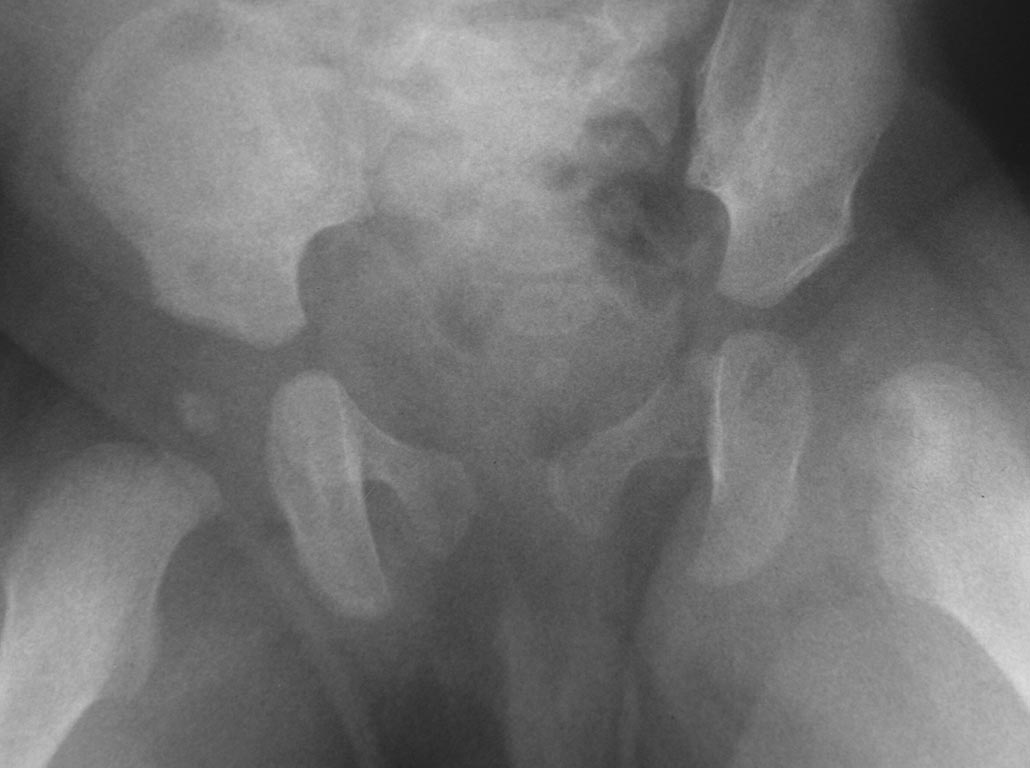

Острый гематогенный остеомиелит головки бедра и ребенка |

Добрый вечер уважаемые коллеги. Помогите советом, в какую клинику и к кому обратится с данной проблемой (у ребенка в возрасте 1мес. диагностирован гематогенный остеомиелит головки бедра).

Лечили консервативно (выписку и фото в динамике прилагаю). На сегодняшний день ребенку 11 мес. Детские ортопеды по месту сомневаются в тактике( в плане операции или выжидательная тактика). Хотелось проконсультироваться с теми кто занимается этой проблемой.